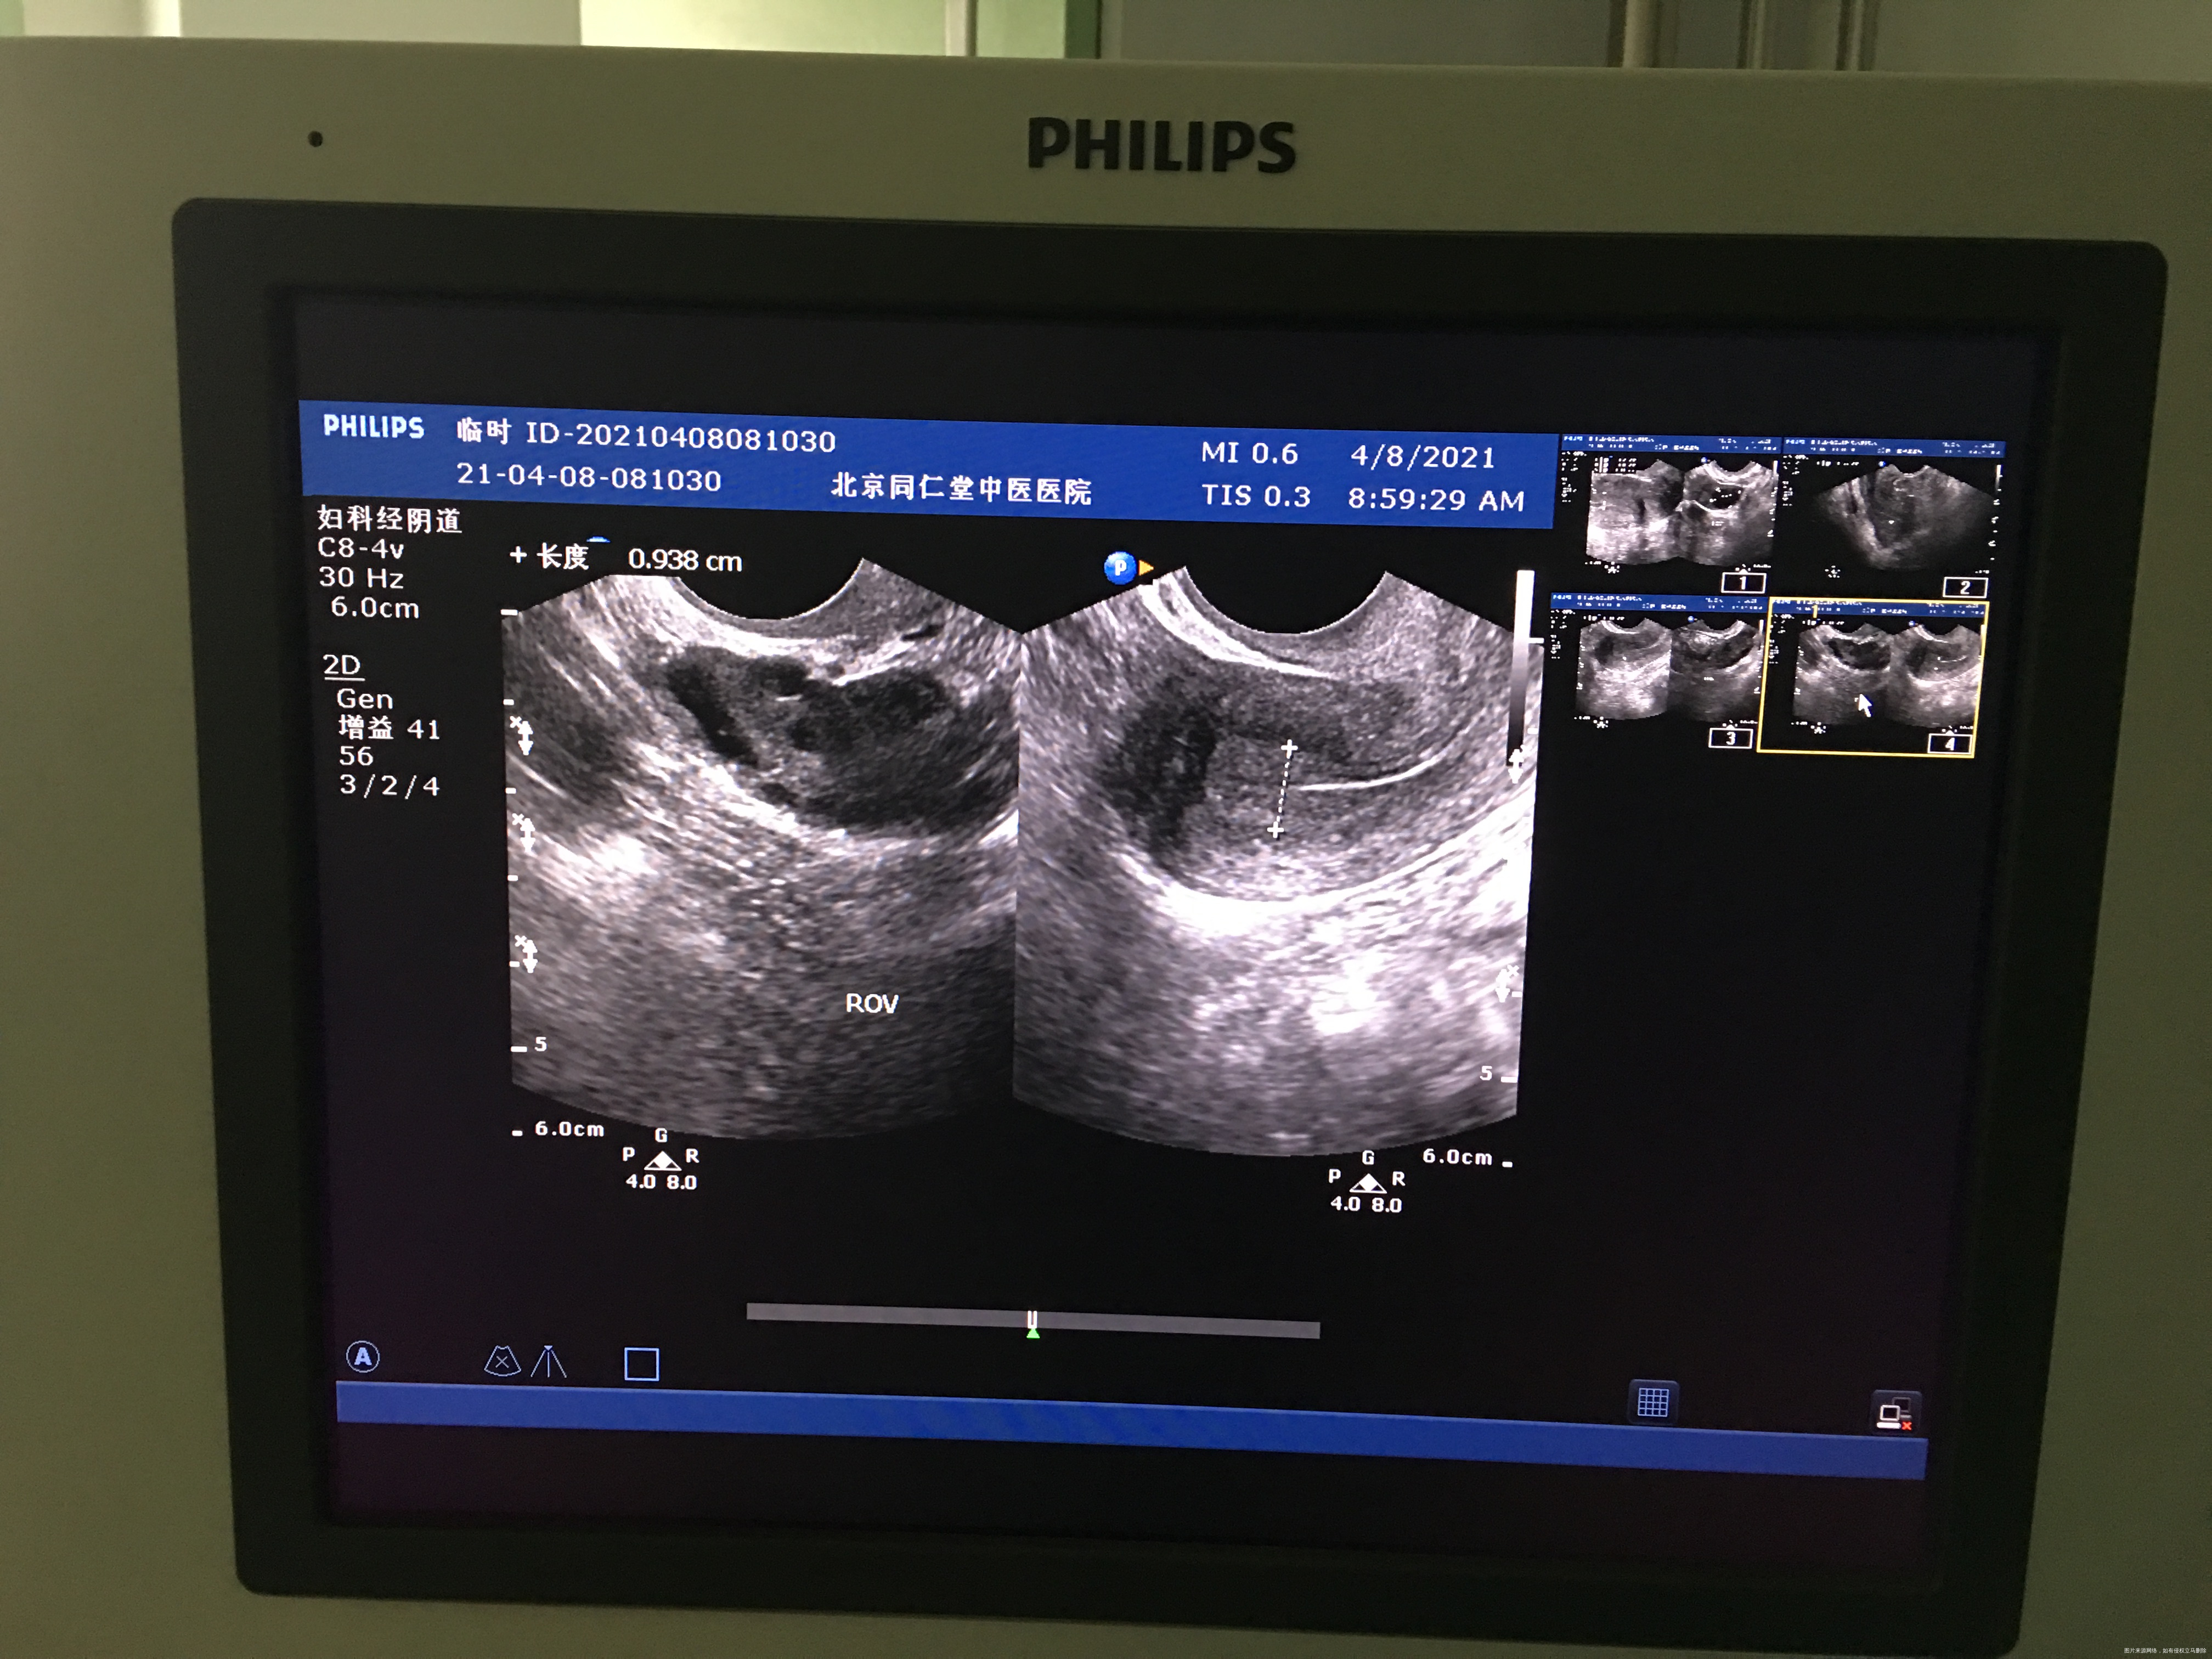

您好,我月经不规律,上次月经3.月2日,请问我现在这个b超显示已经排卵了吗?现在内膜是0.93

你好,根据这个B超没看出来是否已排卵,我只看到卵泡比较多,你应该是有点多囊卵巢,建议医院就诊全面评估治疗!

你好!内膜厚度可以,没有排卵迹象。继续检测卵泡看看。

排卵期内膜厚正常,和卵泡发育不一定同步。成熟大卵泡,排卵后会有一些特征,比如宫腔有少量积液,卵泡膜张力变化等,你的情况不明显,明天再做b超,比较下。

根据B超看不出是否已排卵,排卵后形成黄体,但是很多医院不报告黄体,内膜厚度可以,你可以测个血孕酮值看看,孕酮值大于5考虑已排卵。